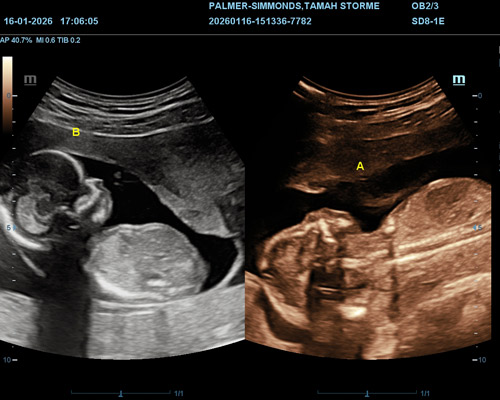

Gender determination in twin pregnancies is usually possible from around 15 weeks of pregnancy. At this stage, both babies are developed enough for the sonographer to identify their genders if their positions allow clear viewing.

- 2D ultrasound to determine your baby’s gender

The genders of twins can usually be identified from around 15 weeks of pregnancy, when both babies are developed enough for clearer imaging.